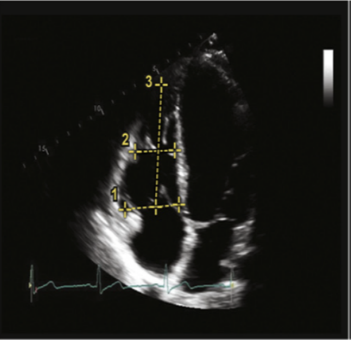

对肺循环而言,我们评价的思维和体循环一致。作为一个低容量低阻力系统,肺循环需要我们关注的点和体循环不同。在非超声评价手段中,我们常规选择PAWP或GEDI作为体循环前负荷的指标,而CVP作为或舒张期右室容积作为肺循环前负荷的指标;左室和右室的射血分数常规作为体循环和肺循环收缩力的评价指标;体循环阻力指数和肺循环阻力指数作为体循环和肺循环后负荷的评价指标。以下将详细阐述重症超声如何评价肺循环系统。首先仍为前负荷的评价。右心室作为唯一一个可以急性扩张的心脏腔室,临床上较难直接测量相关的容积和压力参数作为评价肺循环的前负荷直接指标,更多通过间接征象来评价。选择舒张末右心室的大小测量可作为一个指标。另外,更推荐在舒张末期,心尖四腔心切面,测量右心室面积和左心室面积的比值,若该比值在0.6以内,则表明右心无明显扩张;若该比值在0.7~0.9之间,为中度扩张;若大于1,则代表右心的重度扩张。相关测量示意图如图10所示。舒张末LV与RV面积对比测量示意图如图11所示。